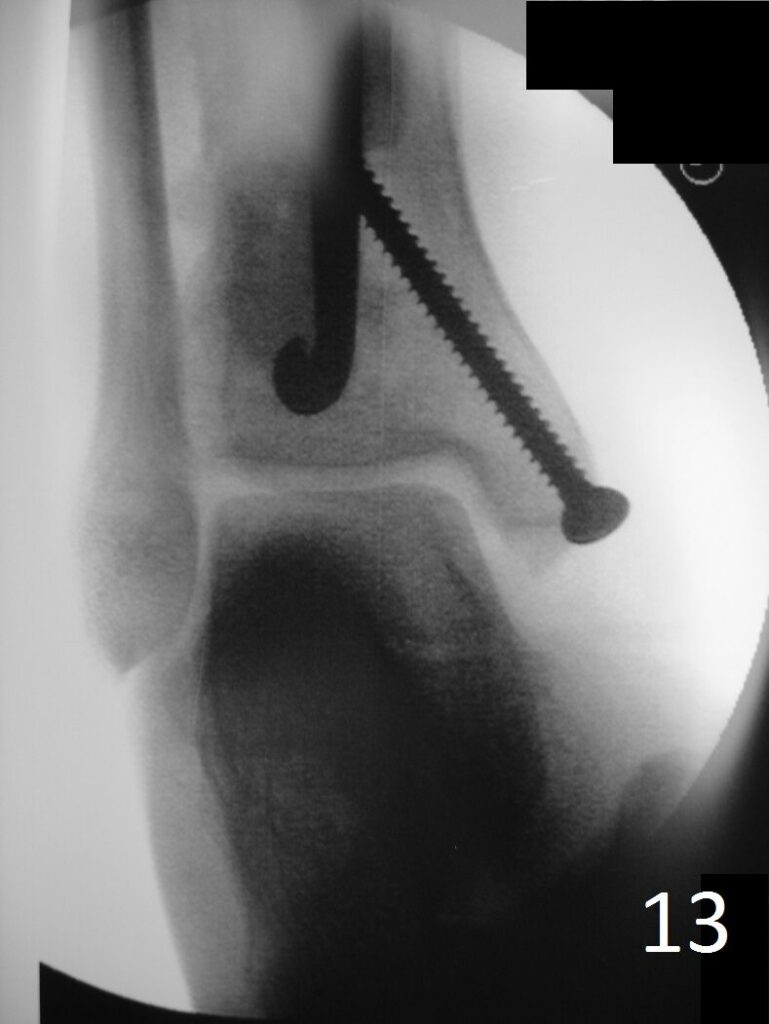

TREATMENT (Fig. 6-12)

• Wide resection recommended

• Possible/low recurrence

• Excision with curettage alone has recurrence rate of 40%

• Addition of cryosurgery to a curettage may lower the recurrence rate

• Role of radiation and chemotherapy are unclear

• Amputation for multiply recurrent tumors or those that are unresectable

Fig. 6-12: Intraoperative photograph of the lesion (Fig. 6) and steps of the treatment (Fig. 7-12), excision, cryosurgery, gross specimen and cemented internal fixation